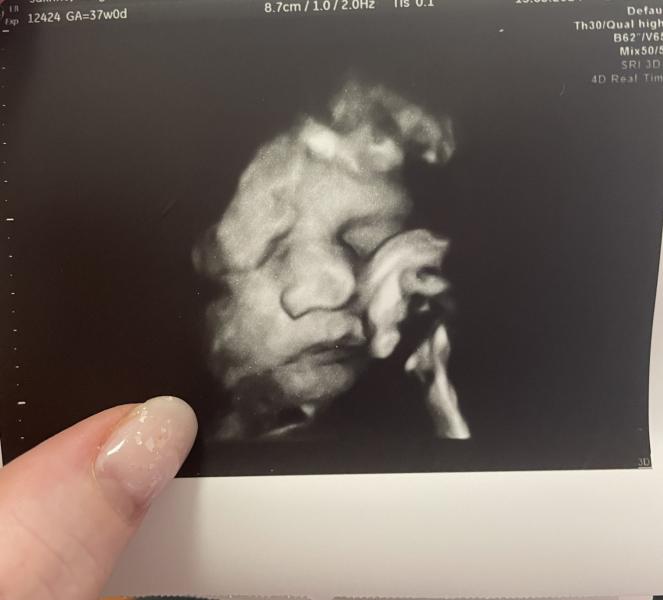

Боже современное узи это просто какое-то чудо.. вчера была на предродовом узи и врач показала сына в 4Д, мое сердце просто растаяло от папиного носа, хомячих щечек и маленьких пальчиков. А уж фото демонстрирующее вокальные возможности это вообще разрыв 😅

Поскорее бы с вами встретиться молодой человек ❤️